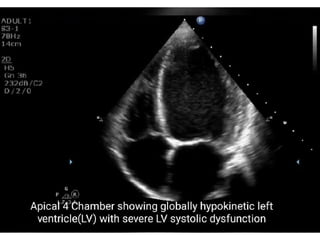

 Echocardiography

 Chest x-ray: shows the signs of cardiomegaly

 History  Echocardiography Chest x-ray: shows the signs of cardiomegaly  ECG: reveals tachycardia, bradycardia and dysarrythmias.  Cardiac catheterization: it is performed to confirm CAD DIAGNOSTIC MEASURES